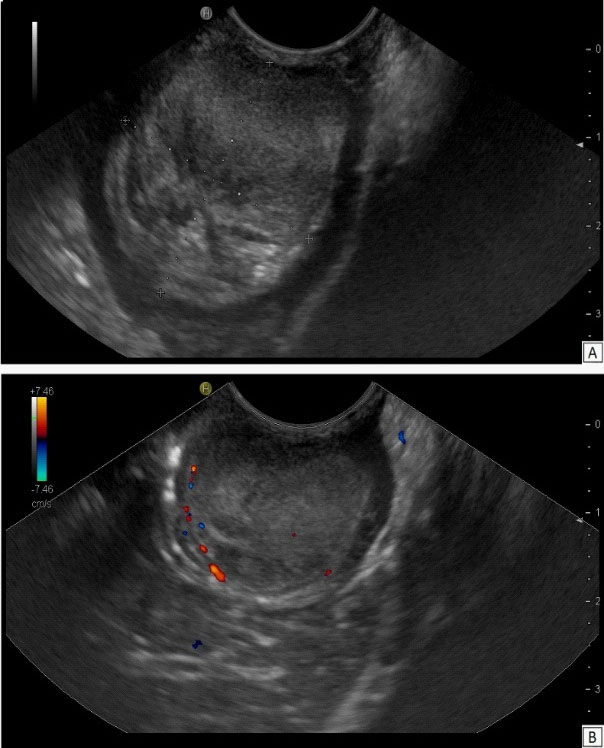

At Endoscopic Ultrasound (EUS) a large bulging lesion about 4 X 2,5 cm in size, located at the anterior wall of the antrum, with a normal-appearing overlying mucosa was detected (Figure 3). The mass, arising from the third layer of the gastric wall, presented an isoechoic lesion, with small hypoechoic foci in the deeper part, without involvement of the muscolaris propria of the stomach and with a weak Color-Doppler signal at the peripheral inner margin (Figure 4). A fine needle aspiration was performed. The tumor, with valve effect, almost completely obstructed the entrance to the pylotus.

Figure 4:Endoscopic ultrasound – (A): Grayscale US image demonstrates an isoechoic mass involving the superficial layers of the gastric wall. (B): Color-Doppler function shows the presence of tine vessels around the lower part of the lesion.